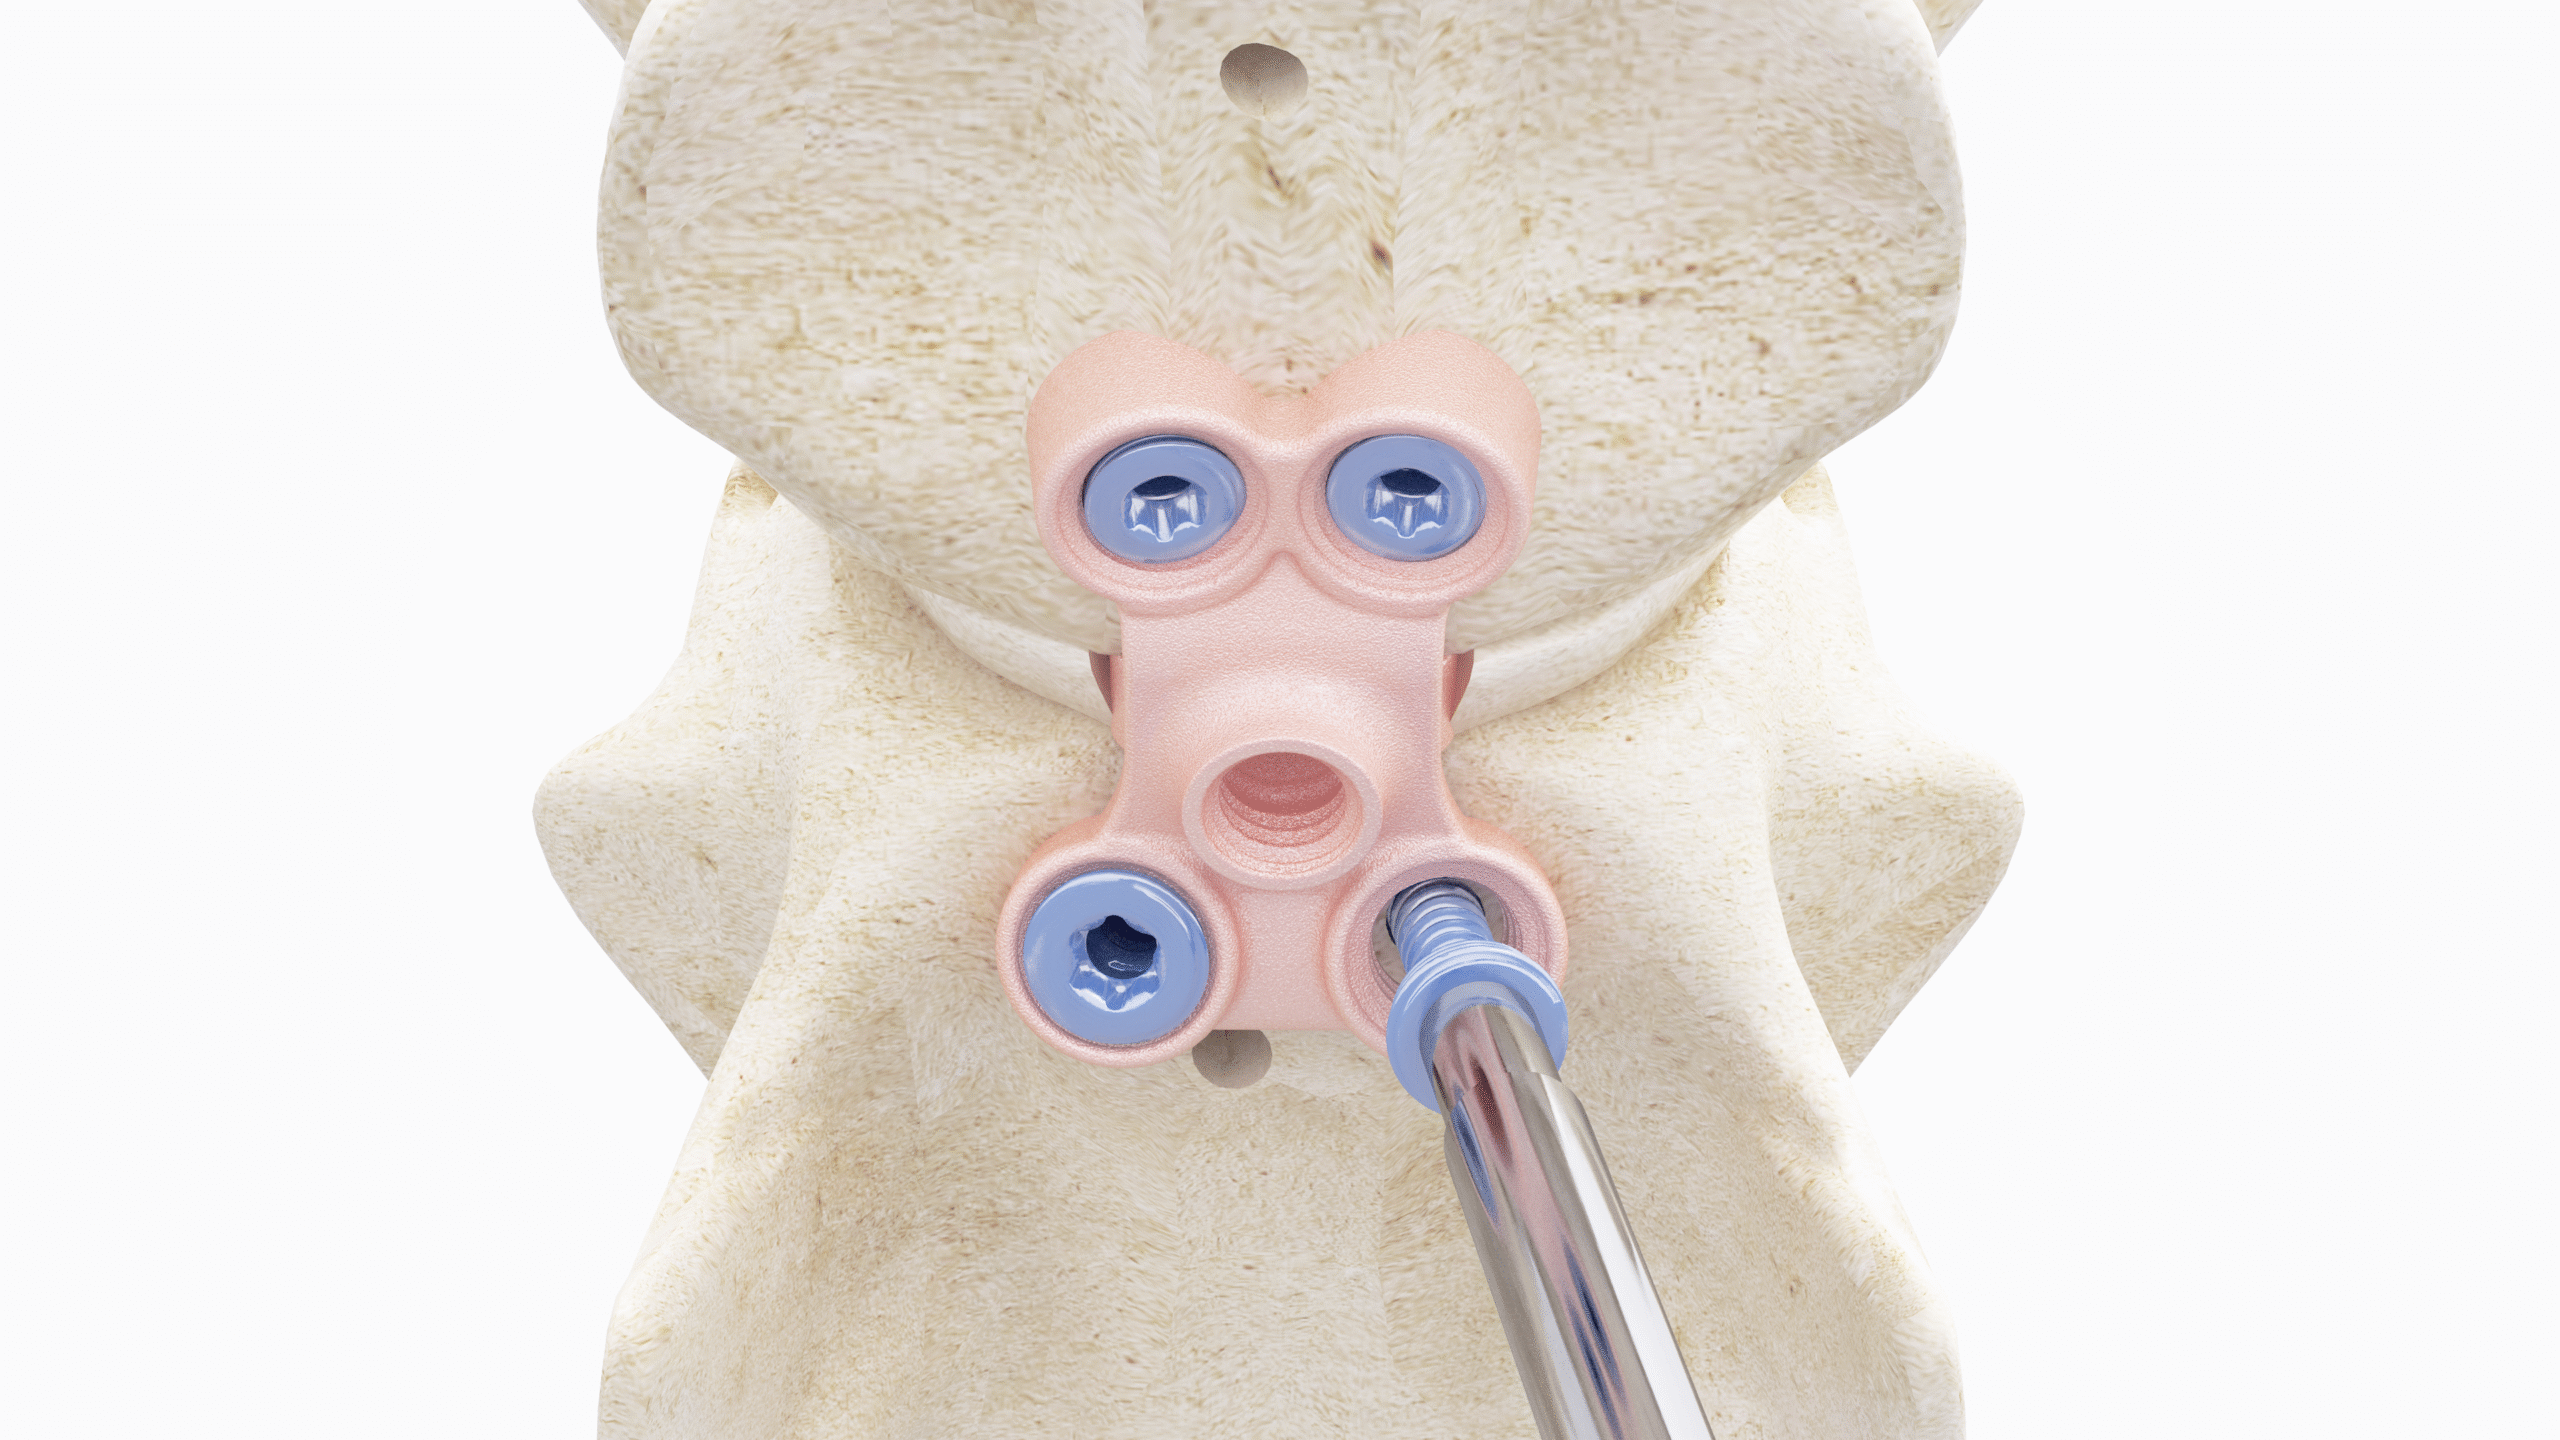

Our CBLO Workshops are designed exclusively for veterinarians seeking to expand their expertise in the Center of Rotation of Angulation-Based Levelling Osteotomy (CBLO) procedure, a surgical technique used to treat cranial cruciate ligament (CCL) rupture in dogs. Our comprehensive program covers stifle anatomy, precise diagnosis of CCL rupture, the correct approach to the stifle joint, thorough stifle examinations, meniscus treatment, the CBLO technique, strategic pre-operative planning, and solutions for potential pitfalls. Combining lectures, demonstrations, and hands-on training with saw bone models and/or cadaveric models, this workshop ensures you acquire practical proficiency under the guidance of experienced surgeons. By the end of the workshop, you will possess a deep understanding of stifle anatomy, the biomechanics of CCL rupture, accurate diagnostic skills, meniscus tear treatment, and the ability to perform CBLO safely and effectively, plan for successful CBLO surgeries, and avoid common pitfalls and complications. Whether you are new to CBLO or seeking to refine your skills, this workshop is ideal for veterinarians dedicated to enhancing their expertise in this area.